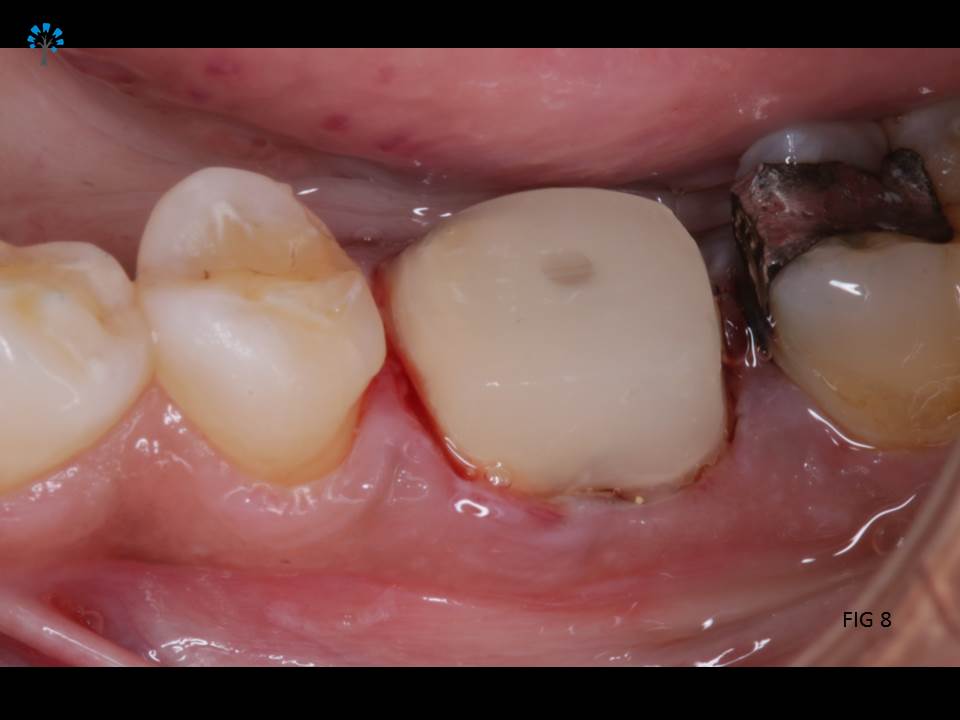

Next step was to build a core structure (Fig 6 shows isolation), in order to place a crown or a cap.

Fiber Post (IVOCLAR*) was placed and the core structure was built.(Fig 7 – 9)

Crown Preparation was done and a digital scan (fig 11) for an impression was obtained.